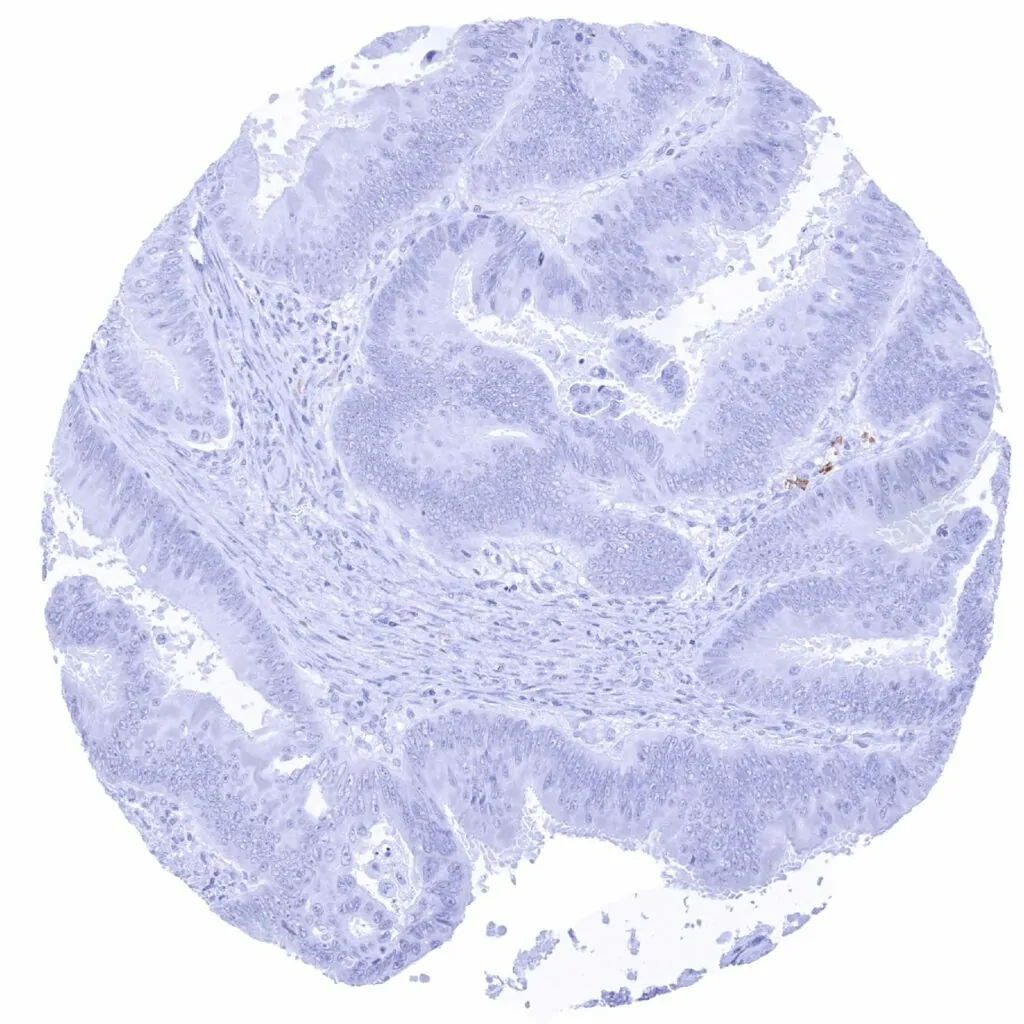

Colon – CD38 negative colorectal adenocarcinoma